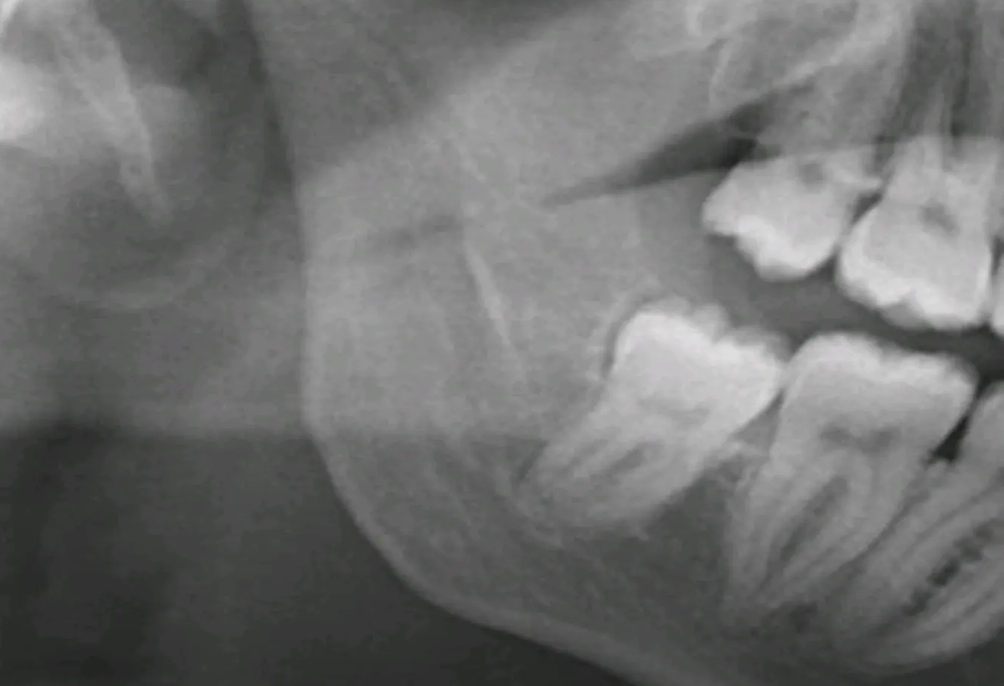

Visdomstandoperation Malmö – trygg behandling hos käkkirurg Visdomstandoperation Malmö är en av de vanligaste kirurgiska behandlingarna vi utför hos Käkkirurgiskt Centrum Skåne. Visdomständer, även kallade tredje molarer, är de sista tänderna som bryter fram i tandraden, vanligtvis mellan 17 och 25 års ålder. Hos många patienter växer de utan problem, men för en stor del […]